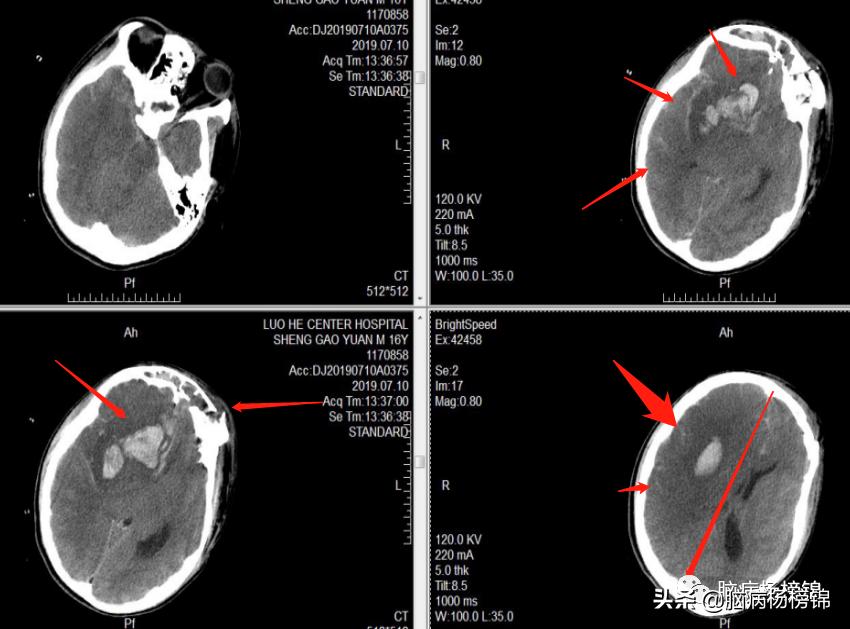

入院后ICU治疗5天患者清醒,转神经外科继续治疗。7月4日CT:

入科第5天7月10日,患者喂食午饭后,家属发现患者心率快,120次/分,值班医生查看:昏迷,四肢肌张力高,考虑癫痫发作,立即给予丙戊酸钠应用,同时查看瞳孔:右侧散大,5mm,光反应消失;左侧2mm,光反应消失。立即复查CT,显示脑内迟发血肿,脑肿胀,中线移位,立即送监护室。